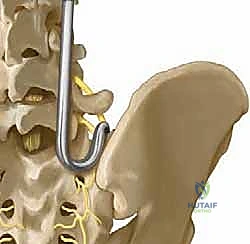

FIG 1 • Anterior view showing position of S-rod or S-hook with reference to L5 nerve root. Notice how the released ileotransverse ligament provides unhindered access.

The L5 Nerve Root

This is our most significant neurovascular concern in this region. The L5 nerve root traverses anterior to the sacral ala. Its trajectory is oblique, progressing from posterior to anterior and superior to inferior, originating from the neural foramen of L5. Crucially, immediately inferior to the L5 pedicle, the nerve passes anterior to the sacral ala, separated by a distance of approximately 1.5 cm. This means any instrument blindly inserted anterior to the ala is at high risk of injuring this root.

This ligament connects the iliac wing to the L5 transverse process. It's a key structure we must identify and meticulously release to gain clear, unobstructed access to the sacral ala. If not adequately released, it can impede proper seating of our instrumentation.